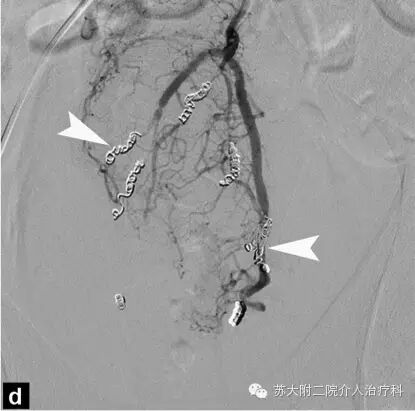

上图所示,我们采用只有1mm粗细的微导管分别进入左右直肠上动脉的远端,置入只有头发丝粗细的微弹簧圈栓塞造成痔疮的血管,结束栓塞后再次造影,可见痔疮血管立即消失。患者的症状也立即得到了改善。